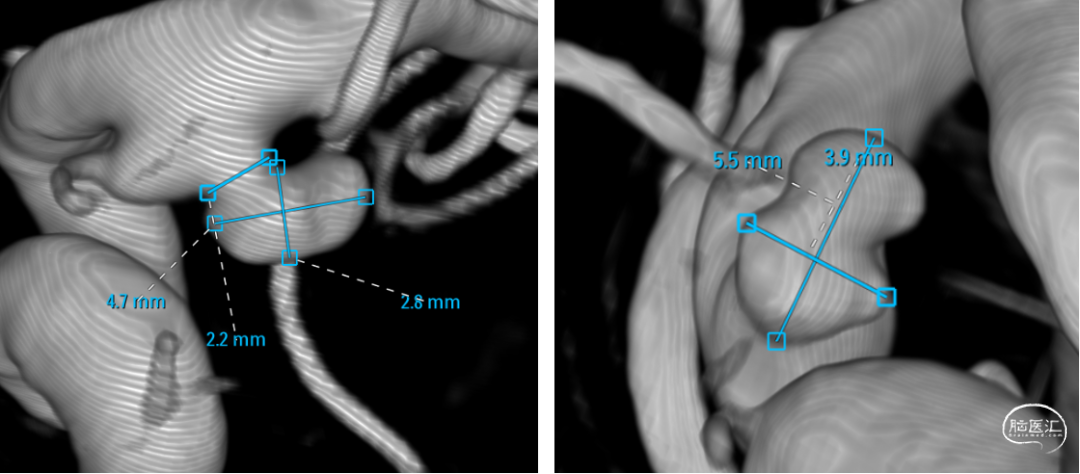

平均宽度(4.5+3.8)=4.2mm,最小深度7.5mm,选择SL5x3

右侧:平均宽度(5.5+3.9)=4.7mm,最小深度2.8mm,选择SL5x2

平均宽度(4.7+3.5)=4.1mm,最小深度3.4mm,选择SL6x2